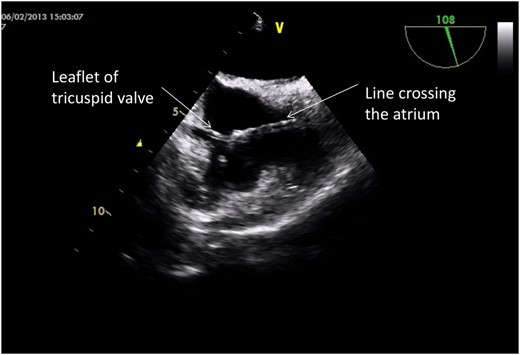

At median sternotomy with cardio-pulmonary bypass, the line was identified with its tip attached to the septal leaflet of the tricuspid valve (Fig. 3). The tip of the line was disengaged, the line removed and the leaflet defect repaired. The patient made a complete recovery, was recommenced on dialysis via a right internal jugular line and discharged home 10 days following the surgery. Unfortunately the patient steadfastly refuses the formation of an AV fistula for vascular access.

Intra-operative picture showing the position of the line traversing the tricuspid valve.